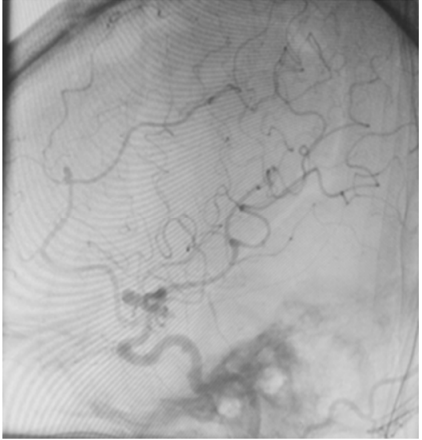

Uma paciente de 66 anos de idade, tabagista, hipertensa com tratamento irregular. Apresentou cefaleia súbita de severa intensidade associada a náuseas. Ao exame físico, observaramse AC = RR2T com BNF, FC = 100 bpm, AP = MVF sem RA, FR = 15 irpm, PA = 182 mmHg x 100 mmHg, SatO2 em ar ambiente = 97%, Glasgow 15, pupilas isofotorreagentes, sem deficits focais. TC crânio e arteriografia a seguir.

Fonte: Acervo pessoal.